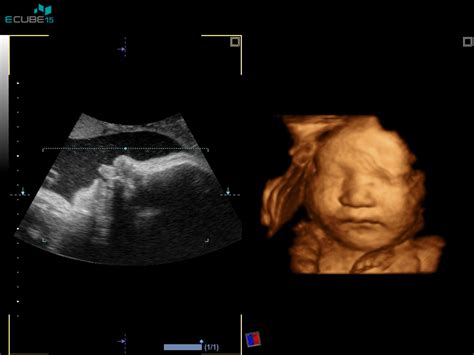

Tradicionalno se je spol otroka zanesljivo izvedelo šele ob rojstvu. Vendar pa sodobna medicina ponuja več možnosti za zgodnejše odkrivanje. Že v času pregleda nuhalne svetline, ki običajno poteka med 11. in 13. tednom nosečnosti, nekatere zdravnice in zdravniki lahko "domnevajo" ali celo z visoko stopnjo gotovosti napovejo spol, čeprav to ni uradni namen tega pregleda, ki je namenjen oceni tveganja za kromosomske nepravilnosti. Napoved spola v tej fazi nosečnosti ni povsem zanesljiva, saj je odvisna od lege ploda in izkušenj ultrazvočnega pregledovalca.

Morfologija, ultrazvočni pregled, ki poteka med 20. in 22. tednom nosečnosti, je običajno prva priložnost za sorazmerno zanesljivo določitev spola. V tem času so se spolni organi že dovolj razvili, da jih je mogoče prepoznati. Vendar pa tudi takrat obstajajo primeri, ko se otrok "skriva" ali leži v neugodnem položaju, kar onemogoči natančno določitev. Nekateri starši se odločijo za genetske teste, kot je NIFTY test (neinvazivni prenatalni test), ki analizira prostocelično DNK ploda v materini krvi. Čeprav je glavni namen teh testov odkrivanje kromosomskih nepravilnosti, pa je informacija o spolu pogosto na voljo že v osnovnem paketu ali na zahtevo.

Nekatere izkušnje kažejo, da je bil spol že v 16. tednu nosečnosti napovedan z veliko gotovostjo, medtem ko so drugi zdravniki spol potrdili šele v 28. ali celo 32. tednu. Zanimivo je, da so nekatere ženske že v zgodnji nosečnosti, celo na podlagi občutka, imele pravilen "predvid" o spolu otroka, medtem ko so se kasnejše ultrazvočne preiskave izkazale za napačne. Tudi zdravnik Pušenjak je omenjen kot tisti, ki je spol lahko napovedal že v 16. tednu nosečnosti, kar kaže na to, da je natančnost odvisna od več dejavnikov, vključno z izkušnjami in tehnično opremo.